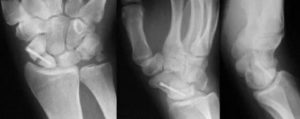

Рис. 28.

Рентгенограммы больного 21 года, оперированного по поводу несросшегося нестабильного перелома ладьевидной кости с выраженным рассасыванием на концах фрагментов, а — через 6 мес после закрытого вправления чрезладьевидно-перилунарного вывиха кисти; б — после пластики трансплантатом из резецированного шиловидного отростка лучевой кости с временной стабилизацией фрагментов и трансплантата спицей.

Рис. 29. Рентгенограммы больного 24 лет, оперированного по поводу нестабильного ложного сустава в дистальной трети ладьевидной кости с аваскулярными расстройствами в проксимальном фрагменте, а — через 5 лет после травмы; б — после пластики цилиндрическим трансплантатом из гребня подвздошной кости с предварительным удлинением лучевого сгибателя кисти, коррекцией положения отломков, стабилизацией кистевого сустава спицей; в — через 14 нед после операции: консолидация.

Рис. 30. Рентгенограммы больного 35 лет, оперированного по поводу ложного сустава в проксимальной трети ладьевидной кости с аваску- лярными изменениями в проксимальном фрагменте, а — через 14 лет после травмы; б — через 16 нед после операции с туннели- зацией фрагментов, формированием ниши между ними и пломбировки спон- гиозной стружкой из метафиза лучевой кости; в — через 7 мес после операции: консолидация с восстановлением структуры проксимального фрагмента и благоприятным функциональным исходом.